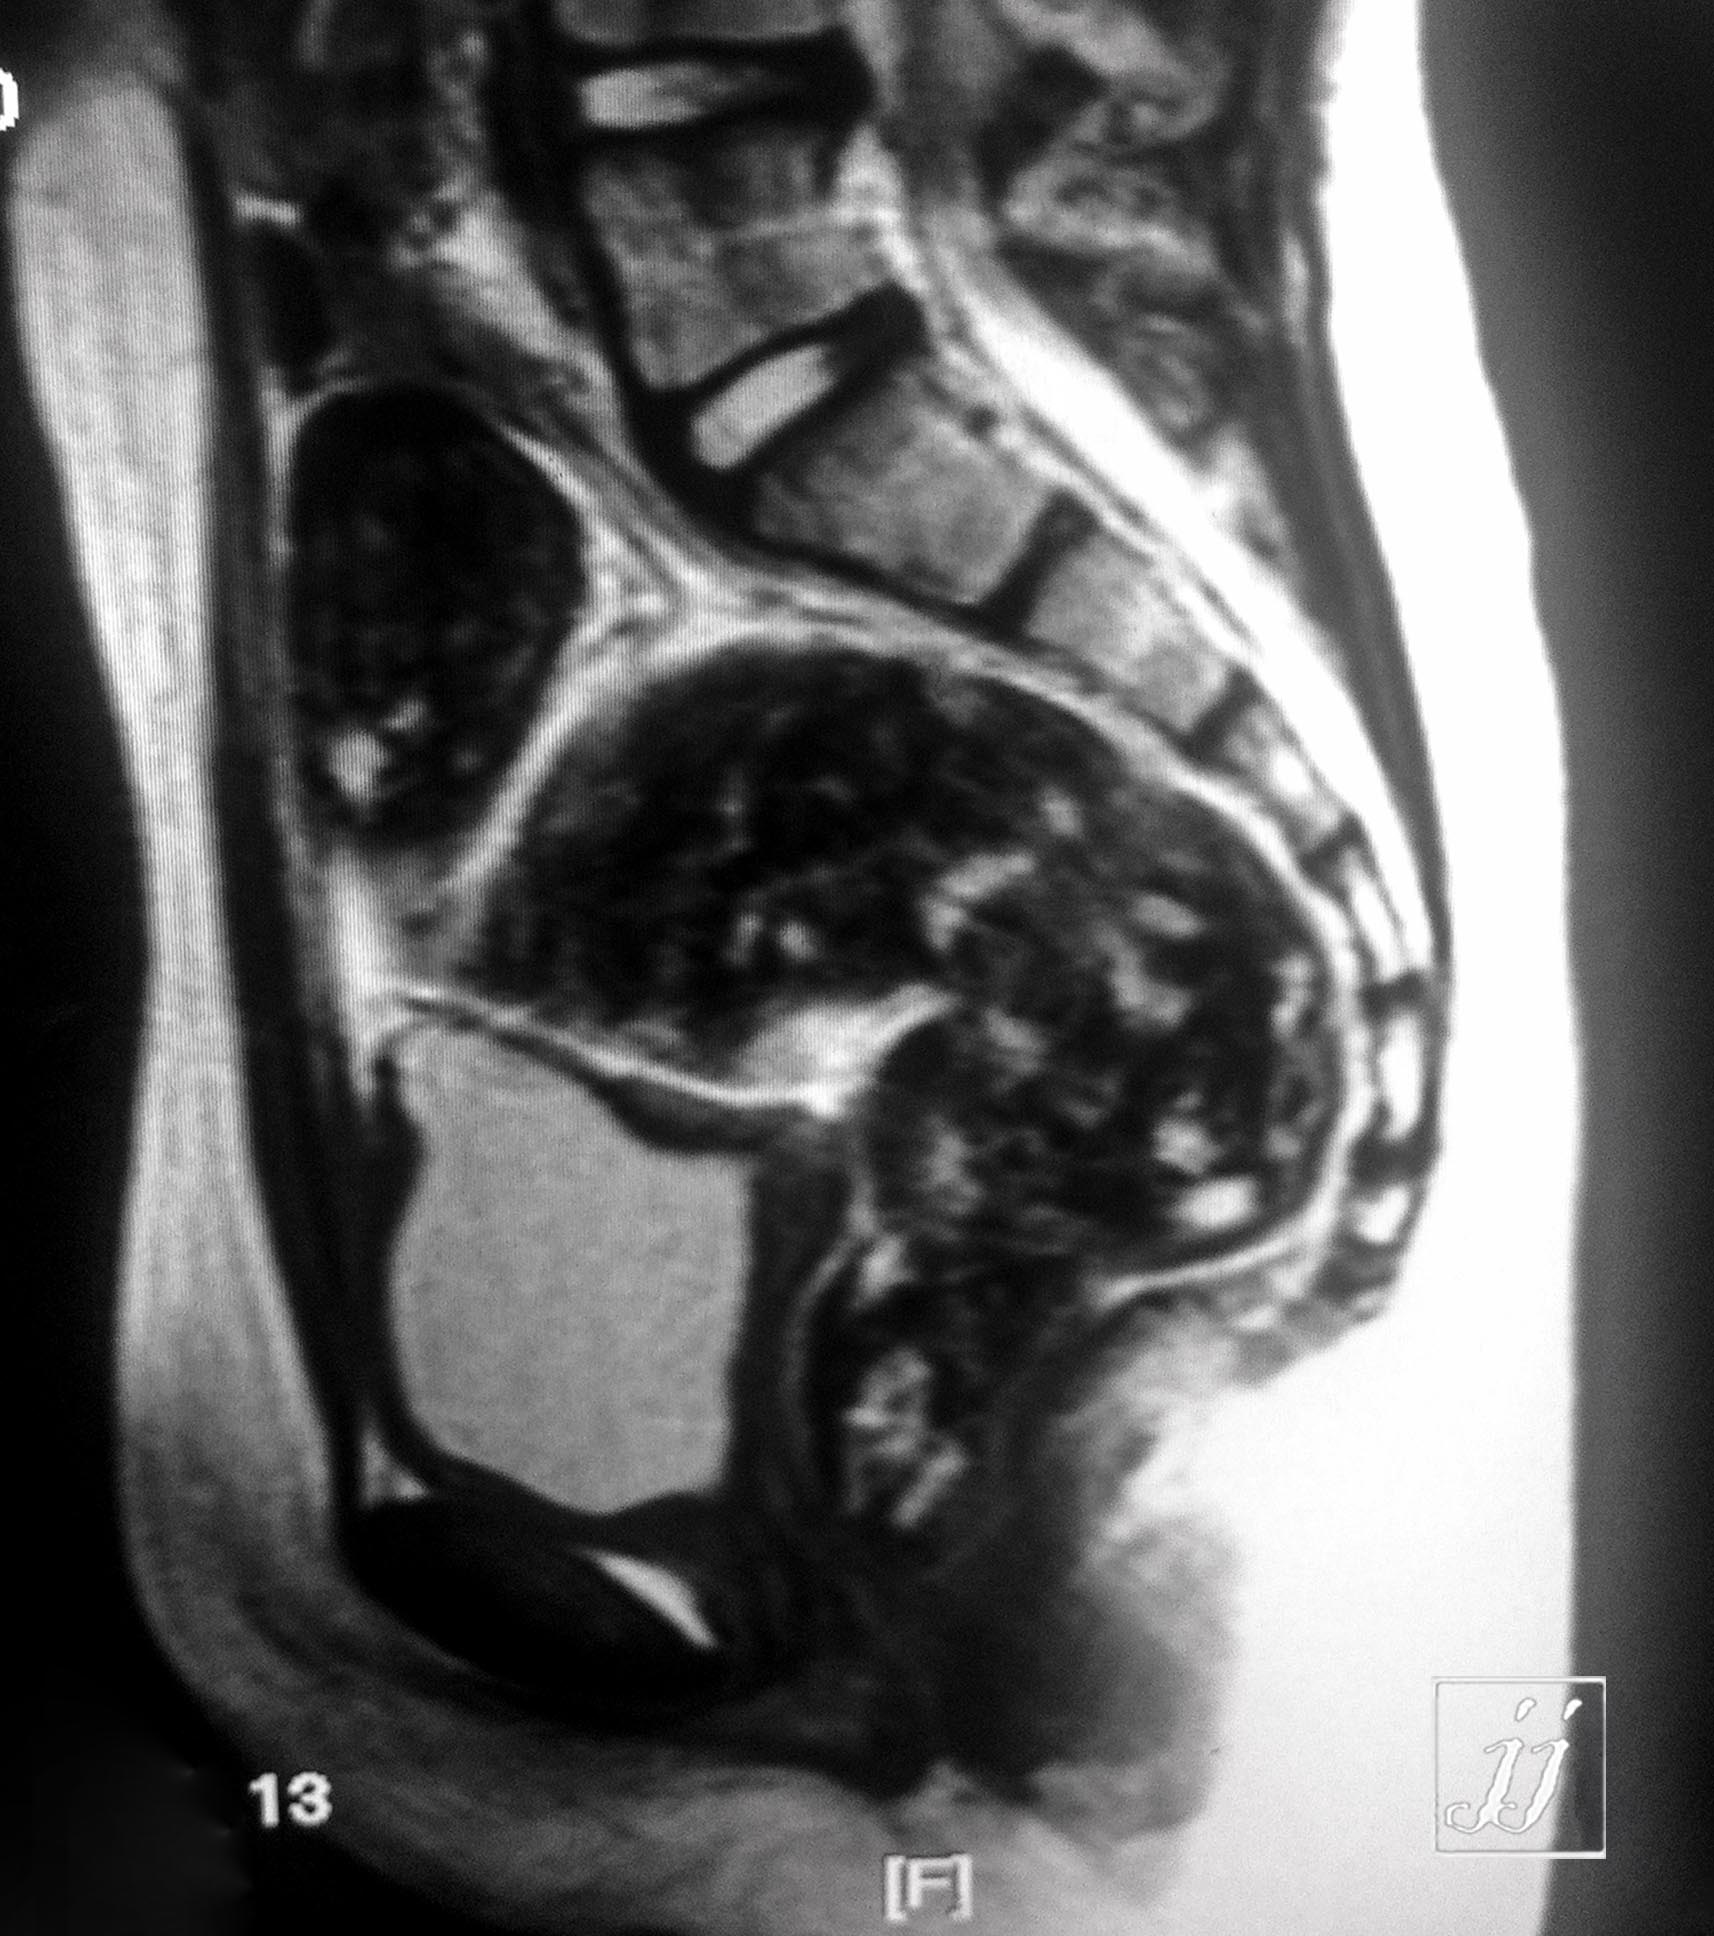

MSK- severe recto sigmoid fecal impaction (1)